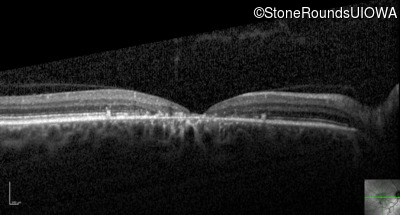

Optical Coherence Tomography - Right - 20/125

Exemplar / OCT Stack

OCT Stack